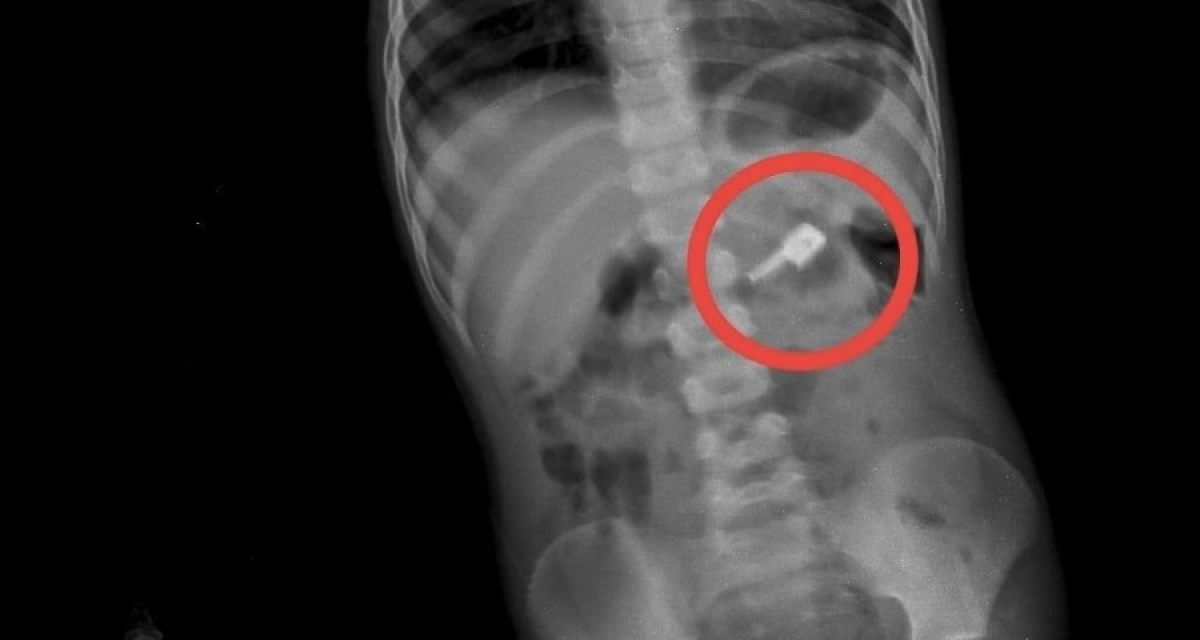

На обзорной рентгенограмме брюшной полости были обнаружены бегунок и, предположительно, две швейные иглы. При проведении процедуры ЭФГДС из желудка удалили одну иглу, бегунок отсутствовал.

«На контрольной R-грамме брюшной полости обнаружили еще две иглы в верхнем этапе брюшной полости и одну — в проекции таза. Провели повторную ЭФГДС и вытащили иглу из желудка. Затем при помощи колоноскопии удалили иглу из сигмовидной кишки», — сообщил хирург.

По словам врачей, мальчик продолжал находиться под наблюдением. На контрольной R-грамме брюшной полости была обнаружена четвертая игла в проекции таза.